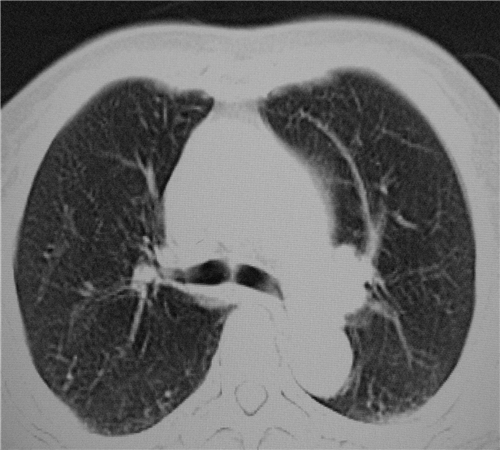

标题: CT26849:女67岁反复胸痛两天余,临床考虑夹层。 [打印本页]

标题: CT26849:女67岁反复胸痛两天余,临床考虑夹层。

双下肺感染,右侧显著。有无夹层,增强扫描后再诊断。

1.考虑双肺感染,右侧为重;2.建议ct增强或mri排除主动脉夹层

双下肺感染,右侧显著。有无夹层,增强扫描后再诊断。食道未见异常。

平扫未见确切夹层征,建议必要时增强扫描或mri检查。